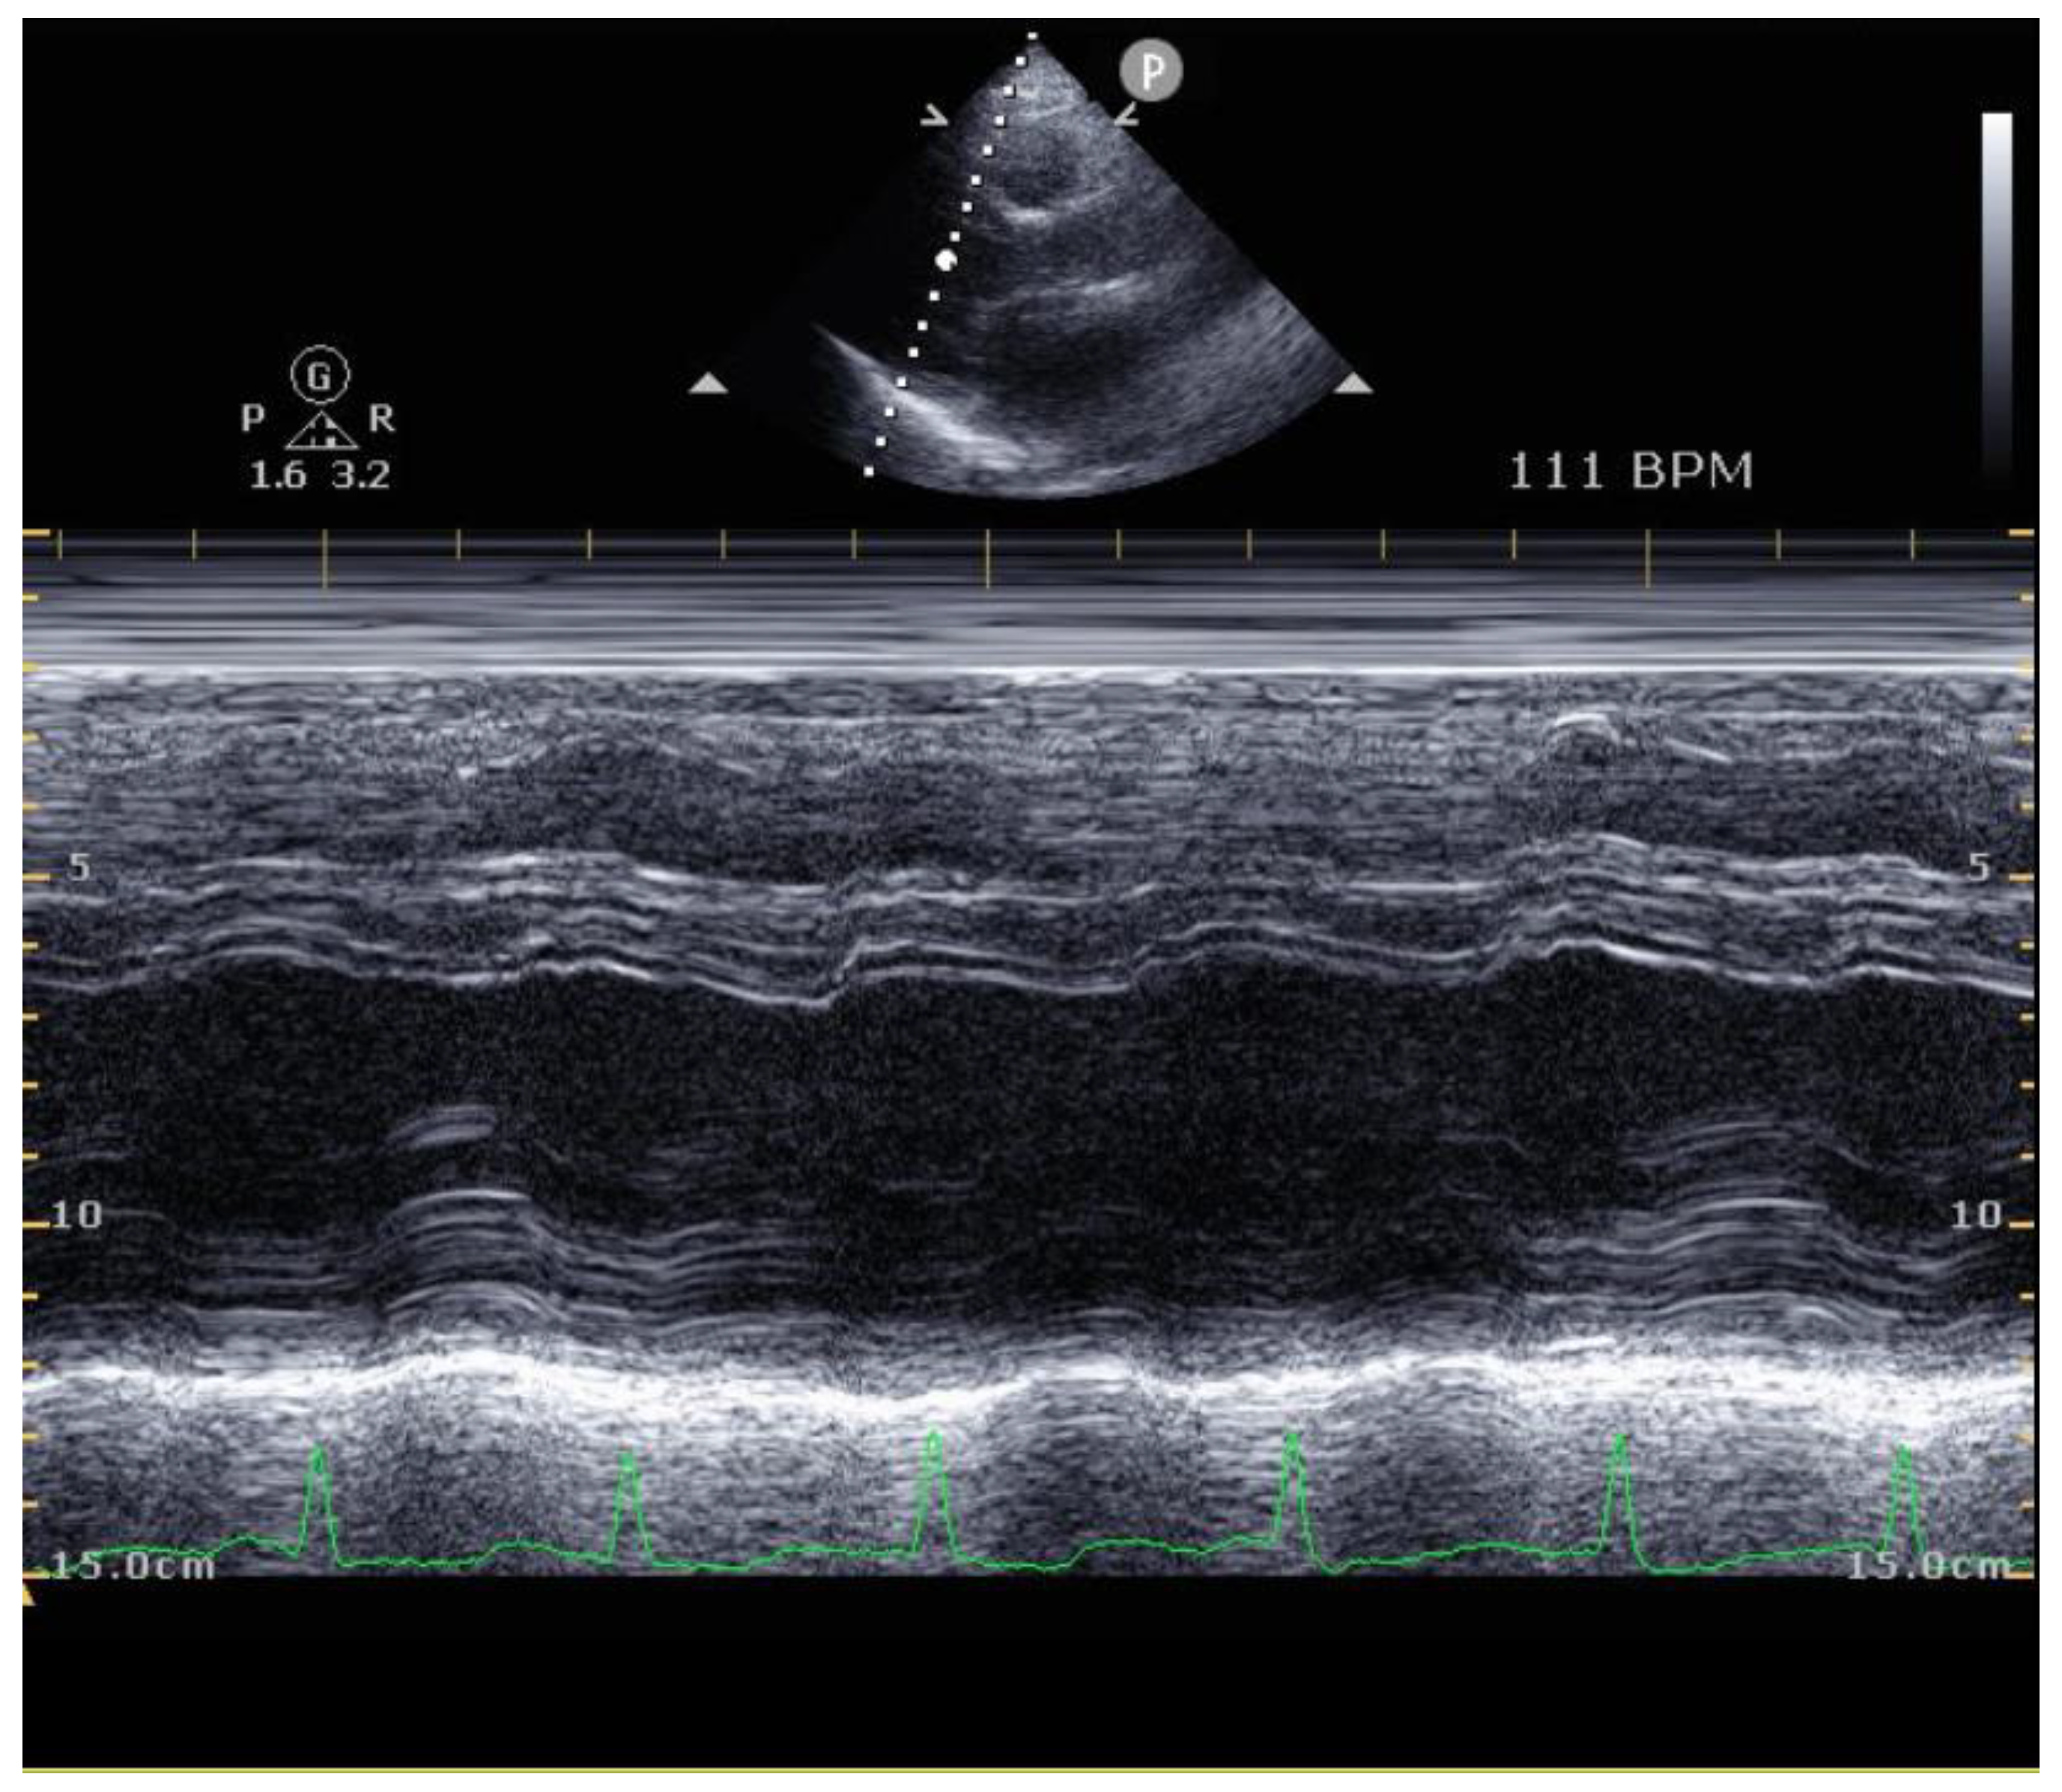

2.4. Echocardiography

| Parameters | Cardiac Rehabilitation Participants (N = 26) | Cardiac Rehabilitation Non-Participants (N = 16) | ||||||

| Initial | 3 months | Δ | p value | Initial | 3 months | Δ | p value | |

| EF (%) | 37.76 ± 8.68 | 46.77 ± 11.82 | 9.01 ± 11.28 | 0.002 * | 36.24 ± 4.03 | 43.64 ± 8.74 | 7.41 ± 8.21 | 0.005 * |

| LVESD (cm) | 4.32 ± 0.88 | 4.04 ± 0.86 | −0.28 ± 0.99 | 0.221 | 4.49 ± 0.81 | 4.22 ± 0.73 | −0.27 ± 0.69 | 0.163 |

| LVEDD (cm) | 5.42 ± 0.62 | 5.45 ± 0.77 | −0.03 ± 0.84 | 0.875 | 5.59 ± 0.66 | 5.54 ± 0.54 | −0.05 ± 0.46 | 0.718 |